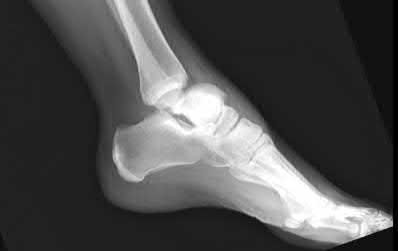

Question 9

A 30-year-old male sustains a severe midfoot sprain. Radiographs reveal widening between the bases of the first and second metatarsals.

The primary ligamentous stabilizer disrupted in this classic Lisfranc injury connects which two osseous structures?

Explanation

The Lisfranc ligament is the strongest ligament in the tarsometatarsal joint complex. It courses obliquely from the lateral aspect of the medial cuneiform to the medial base of the second metatarsal. It acts as the primary stabilizer of the second metatarsal base. Disruption results in the classic widening between the first and second rays, often with an avulsion fragment ('fleck sign').